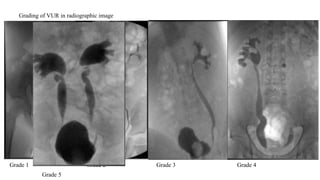

Grading of VUR in radiographic image

Grade 1 Grade 2 Grade 3 Grade 4

Grade 5

Grading of VURin radiographic image Grade 1 Grade 2 Grade 3 Grade 4 Grade 5